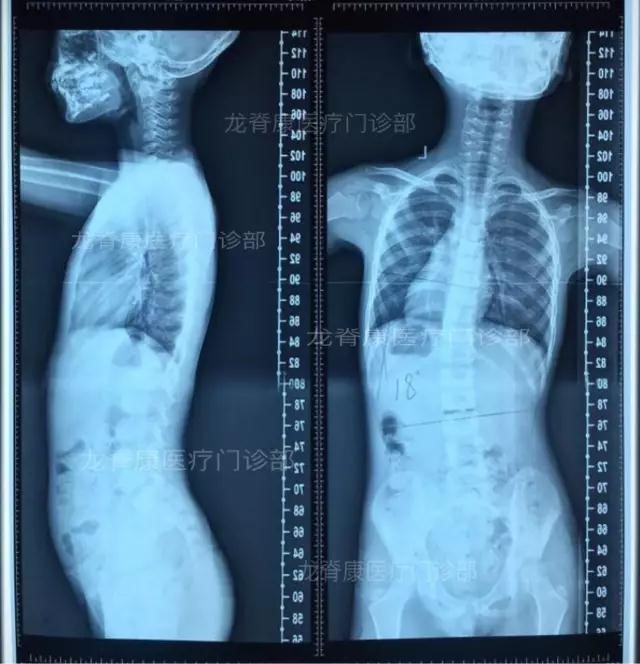

并让孩子拍了X光片: